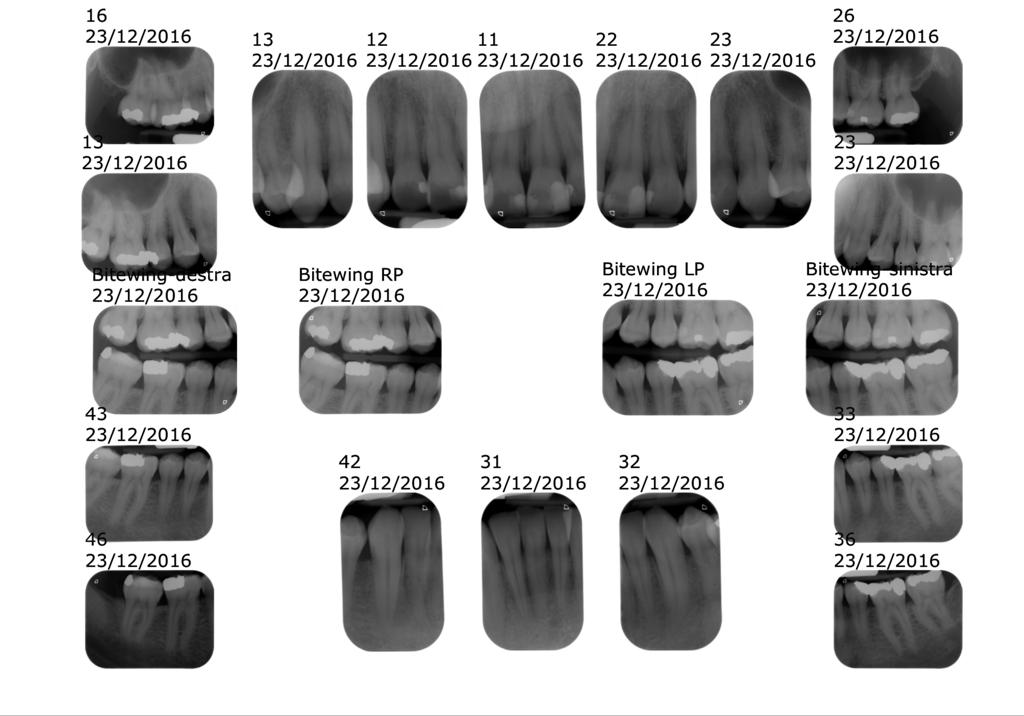

1) Status radiografico:

Vengono fatte delle piccole radiografie che vengono svolte con 20 piccole lastrine.

20 lastrine? Non saranno troppe? Sarà rischioso?

Ti rassicuro subito dicendoti che si tratta di radiografie digitali, grazie alle quali i tempi di esposizione ai raggi sono decisamente bassi.

Noi in studio li usiamo di 0.15 millesimi di secondo (quindi tempi brevissimi).

Questa pratica ci consente di avere una visuale molto dettagliata e molto precisa, a differenza della famosa “panoramica” che spesso viene proposta, ma che non consente di vedere nel dettaglio tutti gli elementi legati a una malattia parodontale.

Grazie a queste radiografie e alle foto dettagliate della bocca iniziamo già ad avere una documentazione precisa che, da una parte ti consente di avere una maggiore percezione dello stato della tua bocca e al contempo permette a me di avere una serie di elementi per fare una diagnosi sempre più precisa.